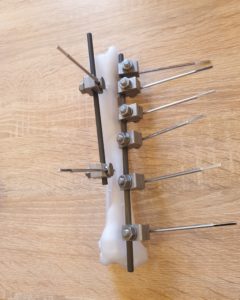

W dniach 25-26.09.2020 w Kuraszkowie odbyły się warsztaty ze stabilizacji zewnętrznej.